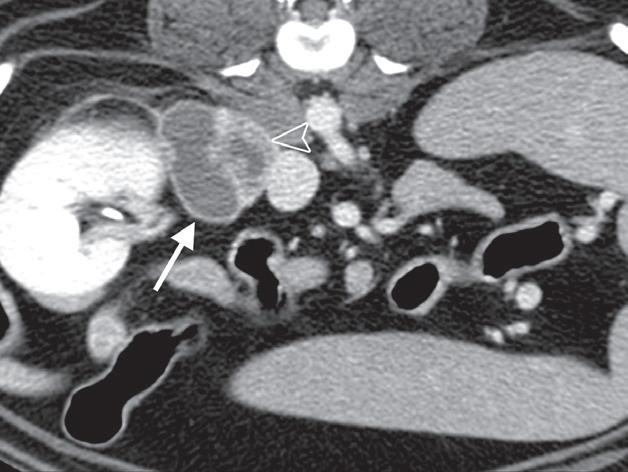

Badanie wykonano u 7-letniego rottweilera z rozpoznanym guzem nadnercza oraz nagłymi objawami dyskomfortu jamy brzusznej. Obrazy na ryc. a–c uporządkowano od strony doczaszkowej do doogonowej. Nadnercze prawe jest powiększone (a, d – otwarty grot strzałki) i ma widoczną ekscentryczną komponentę torbielowatą o densyjności płynu, która rozchodzi się doogonowo (a, b – strzałki). Tkanka miękka rozrostu oraz torebka nadnercza wykazują obwodowe wzmocnienie pokontrastowe. Torbielowata komponenta zmiany rozrostowej widoczna na obrazie odpowiada krwotokowi, który rozciąga się doogonowo w przestrzeni zaotrzewnowej (d). Dobrzusznie od zmiany widoczny jest moczowód (b – grot strzałki). Diagnoza makroskopowa i histologiczna została potwierdzona po chirurgicznym usunięciu zmiany (e – strzałka). Proszę zwrócić uwagę na porównanie obrazu TK zmiany (d) z wyciętym preparatem makroskopowym (f)